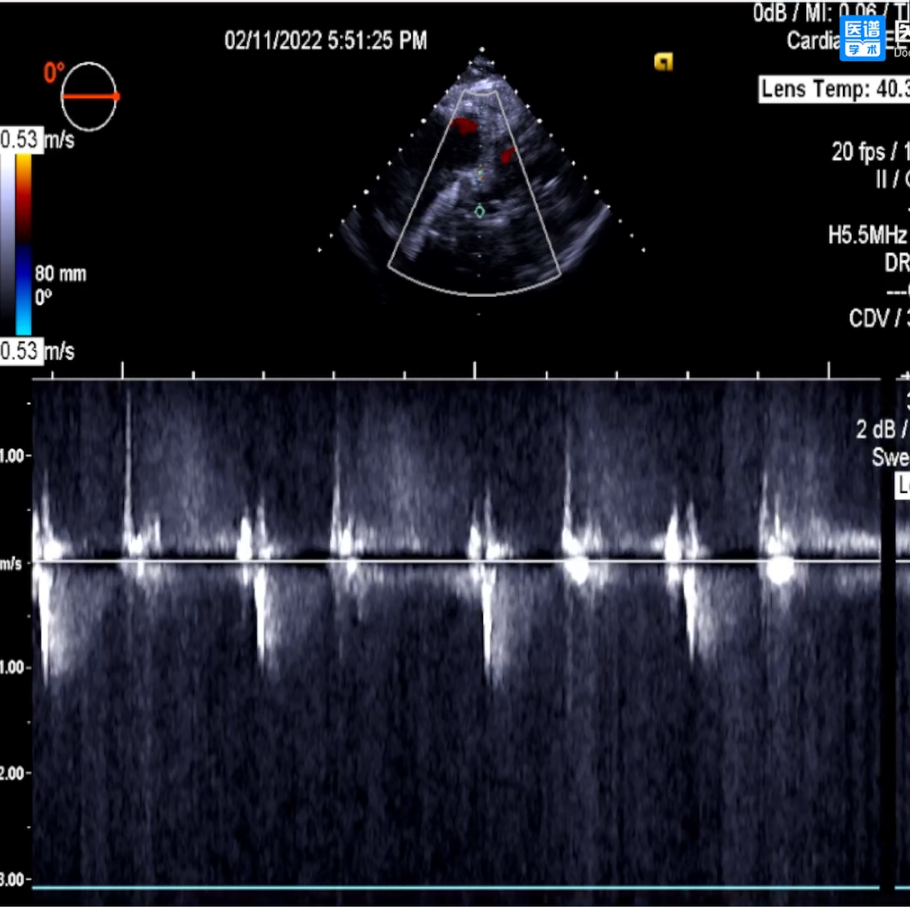

3.直头导丝跨瓣,通过交换导丝将猪尾导管引入左室;超声测得平均跨瓣压差约20mmHg;峰值跨瓣压差30mmHg,流速为2.7m/s;

8.超声平均跨瓣压差约5mmHg,存在少量瓣周漏;